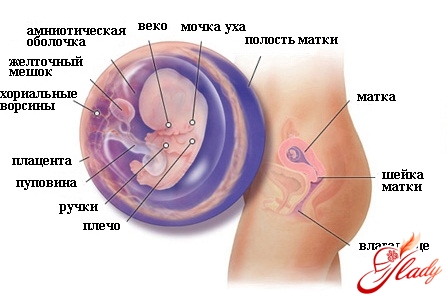

Беременность 8 неделя признаки: На восьмой неделе начинают формироваться ушные раковины, проявляется форма носа и появляется верхняя губа. Хотя на данном этапе беременности глаза по-прежнему широко посажены, на них уже намечаются веки. Желудок опускается в брюшную полость и оказывается на своем месте. Происходит закладка слюнных желез. Если у вас мальчик, то на этом сроке беременности идет формирование его яичек. УЗИ в конце 8 недели позволяет различить у зародыша головной и тазовый концы.

Беременность 8 неделя узи: На этом сроке беременности УЗИ может показать первые спонтанные движения вашего малыша. Уже хорошо видны пальчики и ручки, которые уже начинают сгибаться в запястьях и локтях. Нижние конечности разовьются чуть позже. Также начинают вырисовываться верхняя губа, нос и ушные раковины. Завершает формироваться сердечко — на 8 неделе совершенствуются перегородки между его отделами. Таким образом, улучшается сообщение этого важного органа с крупными кровеносными сосудами.

Если у вас беременность 8 неделя, то на данном этапе длина зародыша от темени до крестца составляет примерно 14-20 мм. Вес — около 3 грамм.